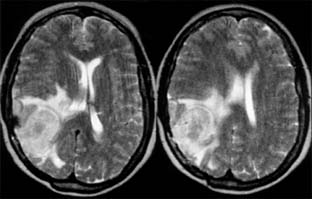

Figure 14-29

Figure 14-29: Axial MRI showing parietal meningioma with secondary cerebral edema.